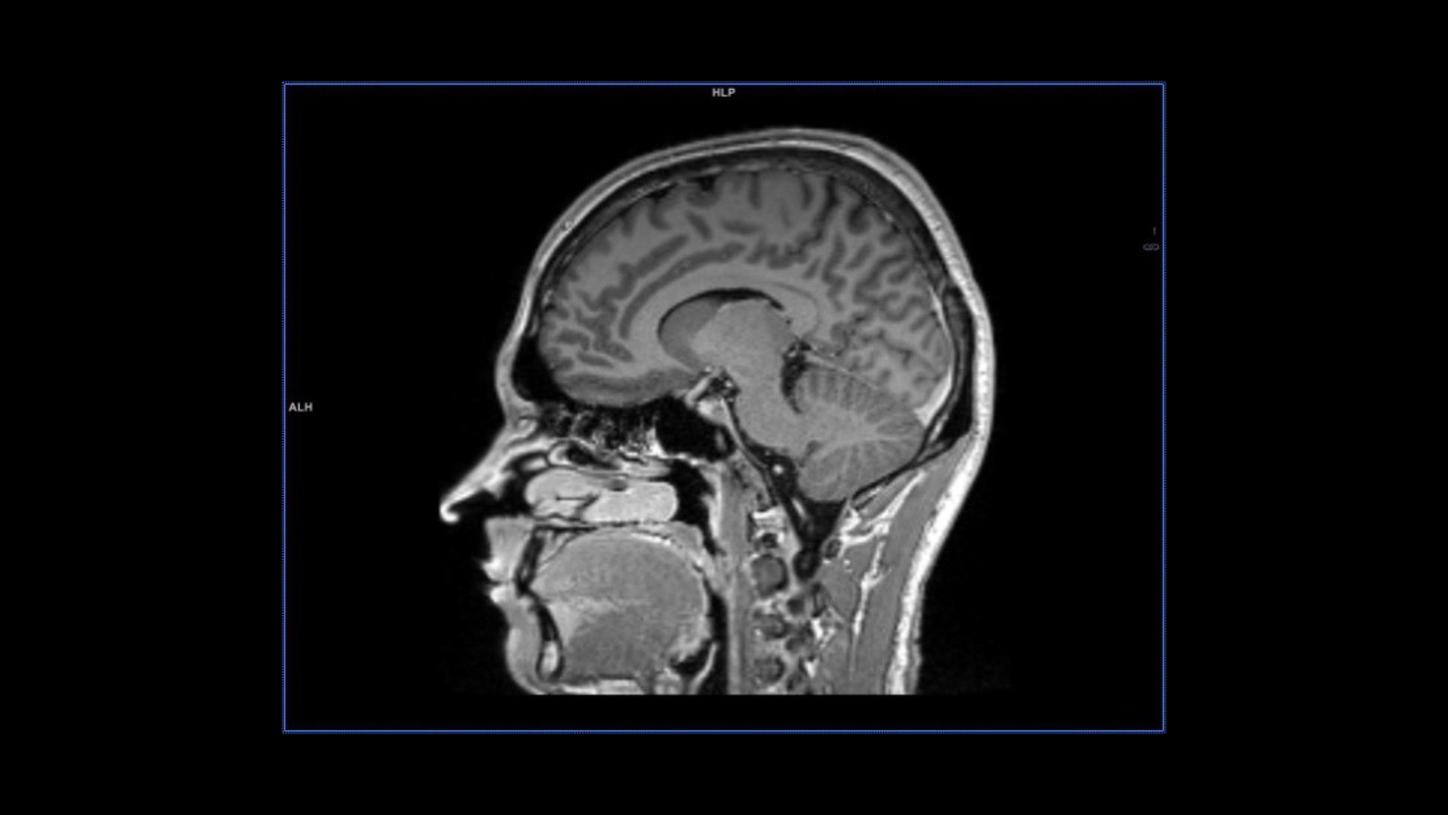

MAGNETOM Sola: T1 contrast sagittal MPRAGE